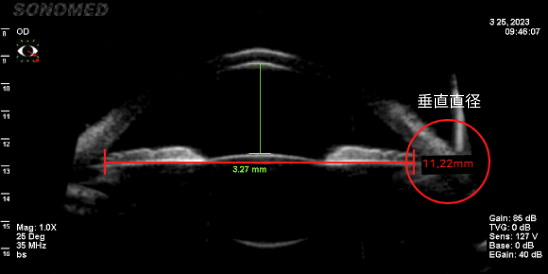

准确测量眼内空间

只有准确测量眼内空间是否足够,才能确定能否手术、晶体尺寸、可最小化晶体旋转概率的植入位置。

由于垂直直径平均比水平直径长,因此垂直型V-Toric ICL是在宽敞的空间内植入尺寸适中的晶体,晶体不接触周围组织,预防了晶体植入手术的副作用并提高了稳定性。

• 水平眼内空间测量(11.01mm)

• 垂直眼内空间测量(11.22mm)

垂直直径空间更广